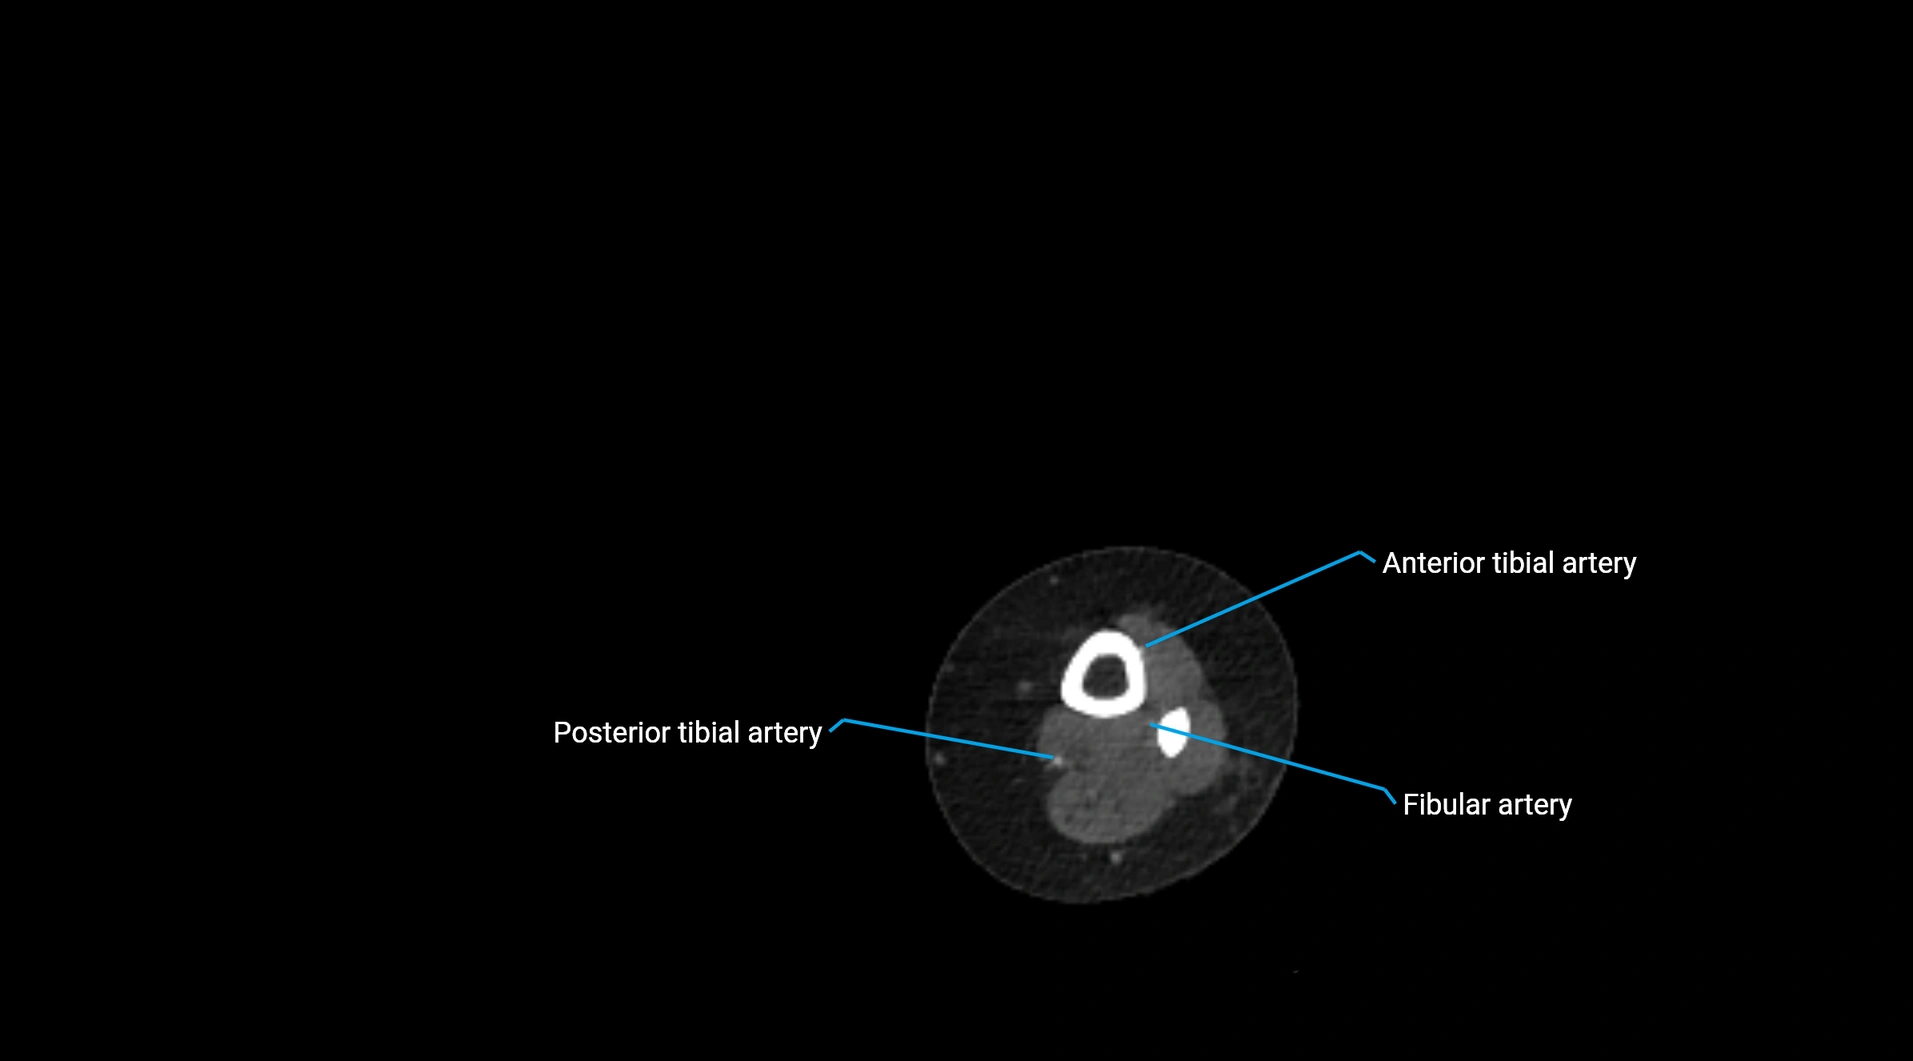

CT images

image

Contrast-enhanced CT (CTA):

• Gold standard for abdominal aortic imaging

• Provides excellent detail of lumen, wall, aneurysm, thrombus, and branch vessels

• Multiplanar and 3D reconstructions help in aneurysm measurement, stent graft planning, and dissection evaluation

• Detects acute rupture, traumatic injury, or occlusion with high sensitivity